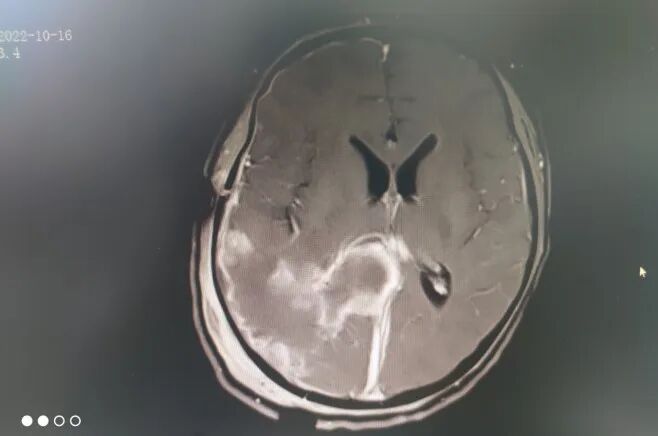

左圖白色為腫瘤,右圖顯示腫瘤全切

然而,好景不長,不到一年時間,小君近日頻繁出現頭痛,再次到醫(yī)院就診,原來罪魁禍首是顱內腫瘤“長大了”。從影像片子上看,這個巨大腦室腫瘤約鵝蛋大小,形似“葫蘆”。

術后,小君被轉入神經重癥監(jiān)護室治療,術后復查CT顯示腫瘤被全切。目前,小君已康復出院,無神經功能障礙。